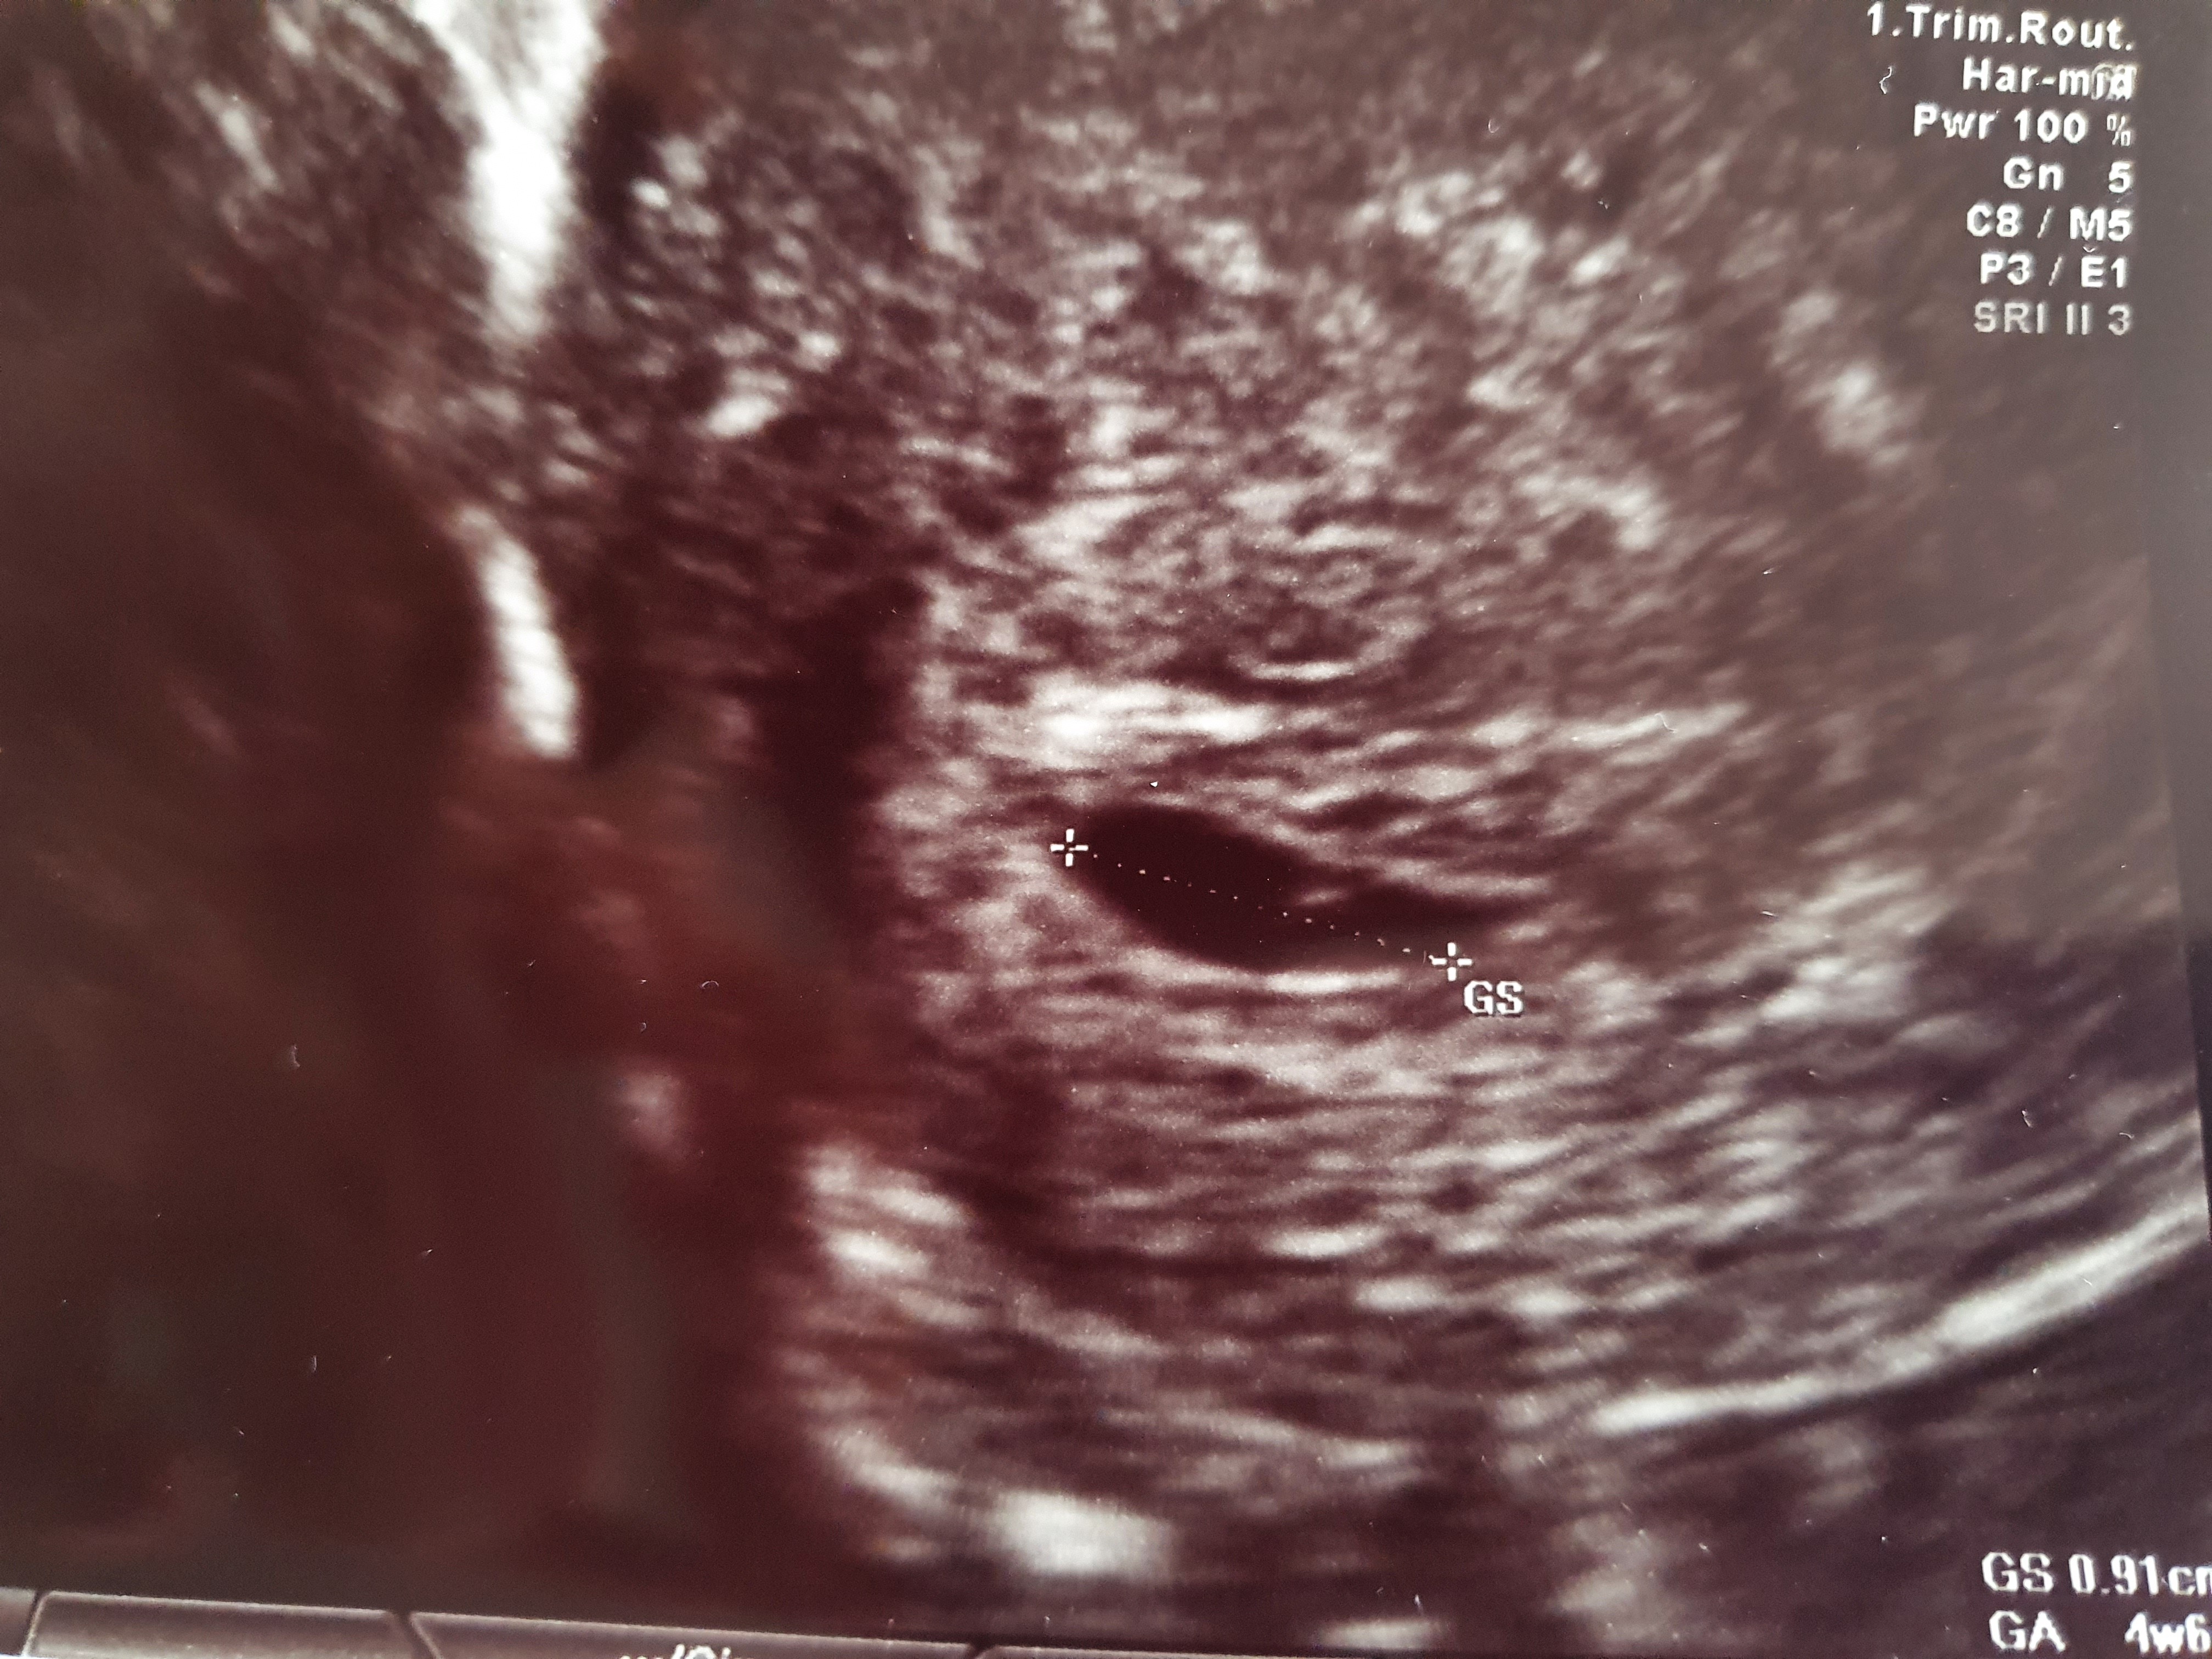

Cześć! Byłam u lekarza, pęcherzyk mam w macicy wg pomiarów 4tc i 6dni, na razie bez zarodka i ciałka żółtego. Już wiem co mam w tym lewym bolącym jajniku - dwie cysty, jedna ma wyrzuty krwi, druga jest jakaś dziwna do obserwacji czy nie jest pozamaciczną. Dzisiaj zrobiłam kolejna betę, za trzy dni mam skontrolować przyrost